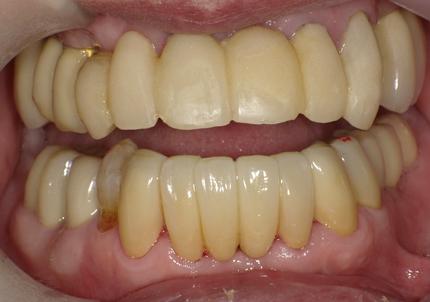

22.最終補綴物完成・装着口腔内写真(2021年1月)

23.自然な形態のインプラント歯頚部

適切な治療計画と治療技術を有することで、このような自然な形態のインプラント歯頚部を形成することができます。

24.口腔内写真

【 2018年 術前 】

【 2025年5月 現在 】